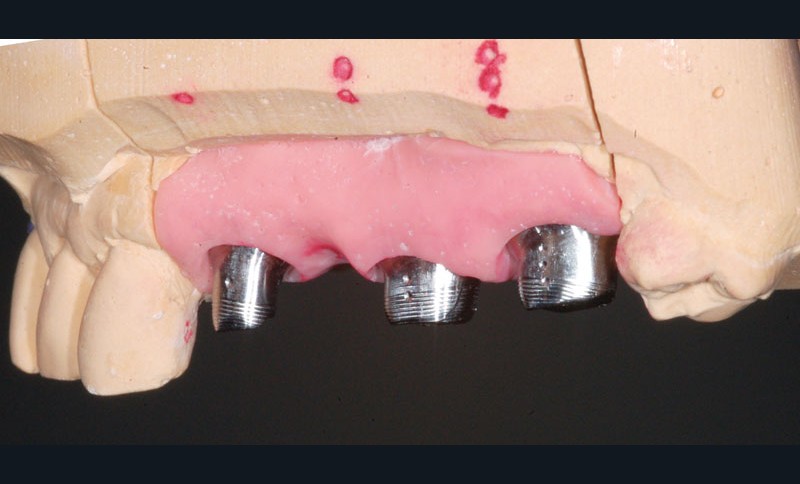

Au maxillaire, 3 implants Astra Tech Implant EV (Dentsply) sont posés en un temps chirurgical. Une empreinte pick-up sera réalisée après 4 mois de cicatrisation.

Une fois les transferts pick-up EV® transvissés, le porte-empreinte Tray, fenestré en regard des transferts, est chargé de matériau monophase Impregum™ Penta™ Soft (3M ESPE). Du matériau est déposé autour des transferts à l’aide d’une seringue. Après dévissage des transferts, ces derniers sont emportés dans l’empreinte et les analogues d’implants sont transvissés.